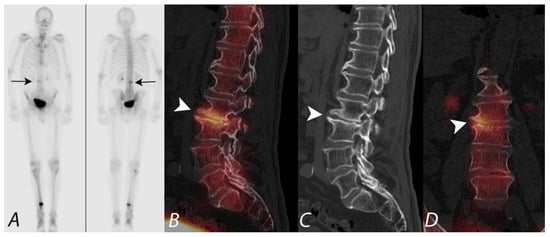

4. Evaluation of Pain of Spinal Origin

5. Evaluation of Postoperative Spine